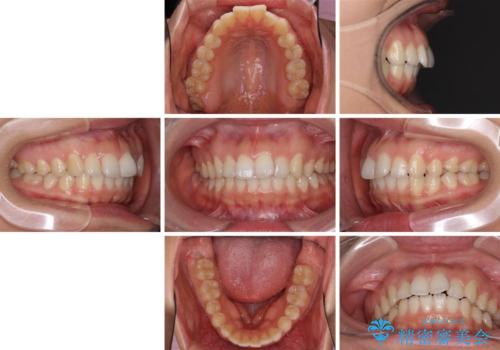

インビザライン矯正で前歯のデコボコを改善

- 前歯のデコボコを気にして来院された患者様です。

目立たないことを最優先にしたいとのことで、デコボコは軽度であったことから、インビザラインにて矯正治療を行うこととしました。

骨格的に下顎骨が左にずれており、上下の正中一致は困難ではありましたが、IPR(歯と歯の間を削る)や後方への移動など組み合わせて、できる限り改善しました。

インビザラインはマウスピースを外している時間が長いと、長期間使用しても前歯のデコボコはあまり改善されません。こちらの患者様は治療期間が長くなり、装着時間が短くなってしまったことで、気になる部分の改善により長期間を要するようになってしまいました。